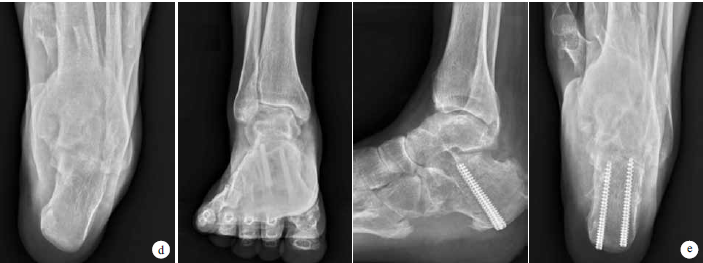

1 典型病例 a术前右足正位、侧位及后位像 b术前右足侧位X线片 c术后1个月右足正位、外侧位、内侧位及后位像 d拆除外支架后跟骨轴位X线片示跟骨内翻 e跟骨矫形术后18个月正位、侧位及轴位X线片

患者 男,27岁。因“重物砸伤致右下肢马蹄内翻足畸形1余年”入院。查体:足跖屈、前足内收、后足内翻畸形,右小腿、足踝部大量贴骨瘢痕。诊断为创伤后右马蹄内翻足。术前AOFAS评分为4分,VAS评分为8分。入院后行右马蹄内翻足Ilizarov外支架矫形术,逐步调整外支架;术后1个月患足跖屈、内收畸形得到纠正,拆除外支架后佩戴行走支具及睡眠支具,但患者后足内翻未得到纠正。6个月后患者再次入院行跟骨截骨矫形空心钉内固定,术后后足内翻纠正。术后18个月随访时走平路、上下楼梯基本正常;AOFAS评分94分,评价为优;VAS评分3分。见图1。